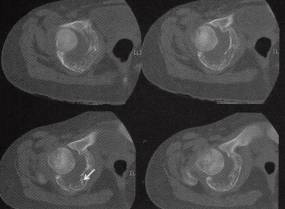

图1右盆骨软骨母细胞瘤

B

C

D

A.CT平扫见髋臼骨质弥漫性小片状低密度病灶,残存骨小梁,多处骨嵴,外缘关节面侧骨皮质连续性断裂、缺失,内缘骨皮质连续性断裂并伴少许骨膜反应,病灶向关节腔内侵犯较明显,关节腔明显积液;

B〜D.CT骨窗见髋曰弥漫性溶骨性骨质破坏、骨皮质缺失及骨嵴,轻度骨膨胀,病灶边缘未见明显硬化